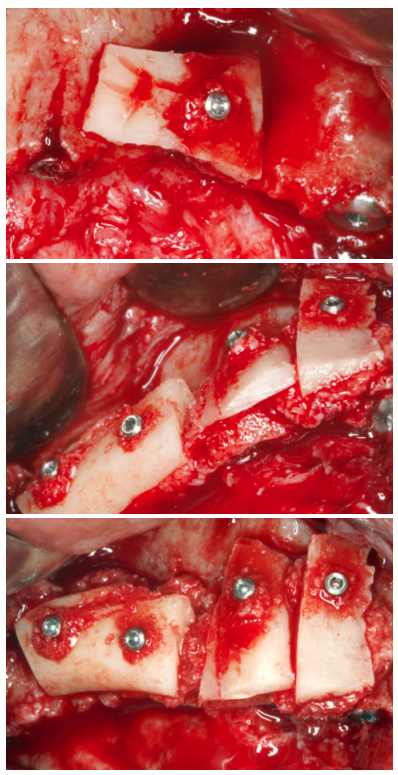

Una vez planificado el caso se procede a la cirugía de inserción de los implantes inferiores, superiores y las diferentes técnicas de aumento de volumen óseo descrito. Se comienza por la cirugía mandibular para obtener hueso autólogo obtenido del fresado que será conservado durante toda la cirugía en PRGF-Endoret fracción 2 sin activar, para ser utilizado en el maxilar donde será necesario para los injertos en bloque, según la técnica descrita por nuestro grupo de estudio19 (Figuras 7 y 8). Una vez obtenido el injerto en bloque será dividido y mantenido en PRGF-Endoret fracción 2 sin activar, para mantener su hidratación y viabilidad celular hasta su colocación según la técnica descrita por Khoury donde se utiliza la cortical del injerto en bloque como encofrado (Figuras 9 y 10)20 .

Finalizada la cirugía mandibular, se realiza la apertura del colgajo superior, donde se constata la gran atrofia en sentido horizontal que existe en determinadas localizaciones, anteriormente descritas, que precisan de la realización de injertos en bloque (Figuras 11 y 12). Se procede a la realización de la técnica de Split en dos fases (Figura 13) con la inserción de los implantes transicionales y la inserción de los implantes que podían ser colocados de forma directa. Una vez terminada la inserción de todos los implantes se fijan las corticales de los injertos en bloque, intentando ser adaptadas a la morfología residual lo mejor posible, evitando aristas que puedan dañar el tejido blando. Una vez fijadas, se rellenan los gaps con hueso autólogo particulado obtenido del fresado de los implantes inferiores, principalmente, así como hueso obtenido del raspado de la rama mandibular (Figuras 14-18).